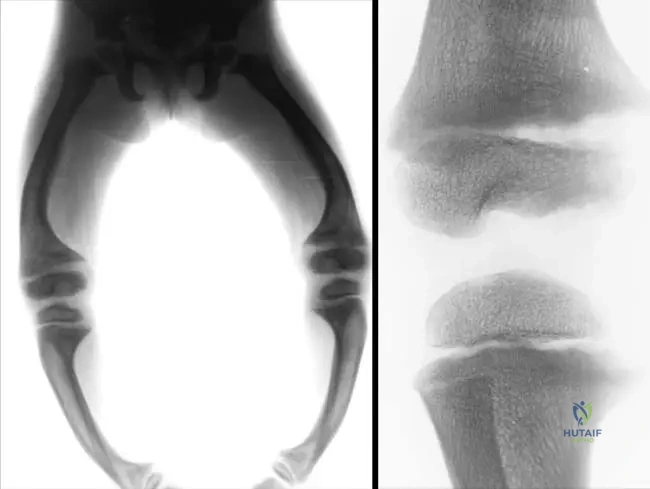

A 5-year-old boy presents with disproportionately short forearms and shins. Physical examination reveals significant shortening of the middle segments of his limbs. Radiographs confirm a chondrodysplasia primarily affecting these regions.

View Answer & Explanation

Correct Answer: C

Rationale: Mesomelic dwarfism is defined as a rare mesomelic chondrodysplasia with an elective defect of the mesial segments of the limbs, which correspond to the middle segments (forearms and shins). Rhizomelic dwarfism affects the proximal segments, and acromelic dwarfism affects the distal segments.

A 12-year-old male with a known diagnosis of Nievergelt type mesomelic dwarfism undergoes a routine orthopedic evaluation. Physical examination reveals limited forearm rotation. Radiographs of the forearm are ordered.

Rationale: The text lists "radio-ulnar...synostosis" as a specific feature of Nievergelt and Langer type mesomelic dwarfism. This fusion would directly explain limited forearm rotation. Radial head subluxation can occur in other conditions but is not specifically mentioned as a primary feature of this type of mesomelic dwarfism.

Question 34

A 9-year-old girl with mesomelic dwarfism, Nievergelt type, presents with progressive bowing of her lower legs and difficulty with ambulation. Radiographs of her tibias and fibulas are obtained.

Correct Answer: B

Rationale: The text explicitly mentions "tibio-fibular...synostosis" as a characteristic feature of Nievergelt and Langer type mesomelic dwarfism. Talo-calcaneal synostosis is a type of intertarsal synostosis, which is also a feature, but tibio-fibular synostosis directly addresses the long bones of the lower leg.